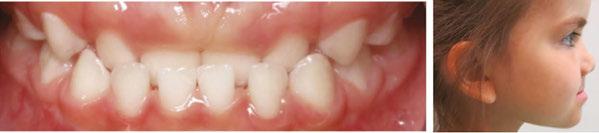

Delayed eruption of both deciduous and permanent teeth in certain special needs children, such as those with Down syndrome, are often seen. In these children, delays in the normal eruption pattern may be up to 2 years.5 Some children with Down syndrome retain their deciduous teeth until up to 15 years of age.5 This commonly leads to both malocclusion and overcrowding.6 These orthodontic issues very frequently lead to serious dental concerns which the dentist must be both aware of and take actions to mitigate their effects. Such actions can include the use of fluoride therapies and an increased amount of time spent educating both the patient and caregiver on oral hygiene techniques.

cally important journal articles pre-dated the 1948 initial published report of an RCT by several decades, it is unreasonable to criticize their usefulness compared to current RCT standards. Developing malocclusions are nearly always first detectable in the primary dentition (ages 2.5-7 years),9,10 nearly always become more complex (i.e., get worse) with age without appropriate intervention,9 and are very frequently co-morbid with pediatric sleep-related breathing disorders (SRBD). In the single-digit growth years they are non-surgically correctible with validated orthodontic/dentofacial orthopedic interventions. It seems reasonable to suggest that failure to diagnose and appropriately treat or refer afflicted young children is a medically-indefensible position.